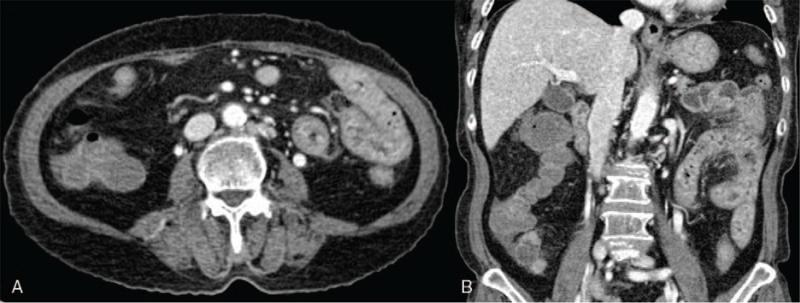

A 74-year-old female without any underlying disease presented to our emergency department as she was suffering from lower abdominal pain and diarrhea for 3 weeks. The patient was diagnosed with infectious colitis, and antibiotic treatment was administered at a local clinic. At presentation, the patient had rashes on both lower legs that developed after the antibiotic treatment, which was assumed as a drug eruption. Although antibiotic treatment was continued, the patient had persistent abdominal pain, diarrhea, hematochezia, and rashes. Proteinuria was developed on urinalysis.

Sigmoidoscopy revealed easily bleeding erythematous mucosal lesions from the descending colon to the rectum. IgAV was suspected, and thus skin biopsy was performed. Histological findings of the skin biopsy showed leukocytoclastic vasculitis, which is compatible with IgAV. A nonsteroidal anti-inflammatory drug was administered for abdominal pain. The patient showed persistent proteinuria and a systemic steroid (prednisolone 50 mg [1 mg/kg]) was started.

一名 74 岁女性,无基础疾病,因腹痛和腹泻 3 周就诊于我院急诊科。患者被诊断为感染性结肠炎,并在当地诊所接受抗生素治疗。就诊时,患者双小腿出现皮疹,出现在抗生素治疗后,被认为是药物性皮疹。尽管继续使用抗生素,但患者仍持续腹痛、腹泻、血便和皮疹。尿液分析显示蛋白尿。

乙状结肠镜检查显示从降结肠到直肠的红斑性易出血黏膜病变。怀疑为 IgAV,因此进行了皮肤活检。皮肤活检的组织学发现为白细胞碎裂性血管炎,符合 IgAV。给予非甾体抗炎药治疗腹痛。患者持续蛋白尿,给予全身性皮质类固醇(泼尼松龙 50mg[1mg/kg])。